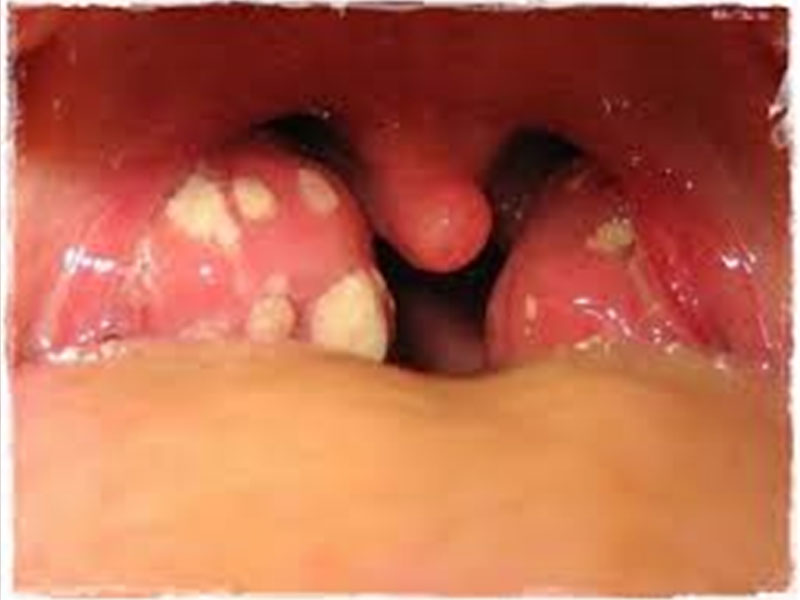

HERPANGINA

- La herpangina es una infección causada por un virus. Ocasiona pequeños puntos rojos que aparecen en la parte posterior de la boca. Esos puntos se transforman luego en pequeños sacos llenos de líquido (ampollas), que se revientan rápidamente y dejan pequeñas úlceras o llagas. Las úlceras son muy pequeñas, de 2 a 4 milímetros de ancho. Pueden ser muy dolorosas y hacer que su niño rechace la comida y el agua.